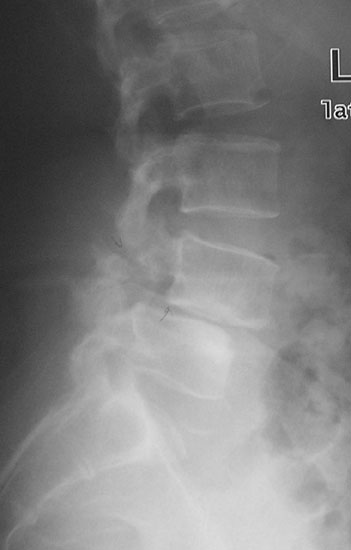

Spondylolisthesis malformations

Spondylolisthesis implies slippage of one lumbar vertebra over the next one, causing pain and nerve compression. Patient can also have difficulty in walking and numbness of the legs. Usually these patients need evaluation lumbar spine by MRI and CT scan, followed by spinal instrumentation and fusion.